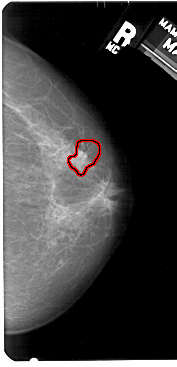

A_1520_1.LEFT_CC

LEFT_CC LINES 5416 PIXELS_PER_LINE 2701 BITS_PER_PIXEL 12 RESOLUTION 43.5 NON_OVERLAY

FILE: A_1520_1.RIGHT_MLO.OVERLAY

TOTAL_ABNORMALITIES 1

ABNORMALITY 1

LESION_TYPE CALCIFICATION TYPE PLEOMORPHIC DISTRIBUTION CLUSTERED

LESION_TYPE MASS SHAPE IRREGULAR MARGINS SPICULATED

ASSESSMENT 4

SUBTLETY 3

PATHOLOGY MALIGNANT

TOTAL_OUTLINES 1

BOUNDARY